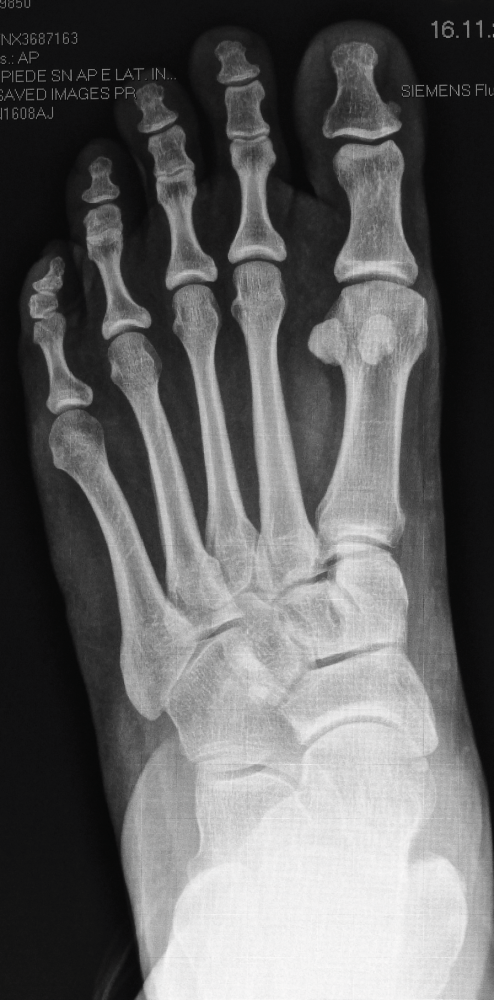

Röntgenbilder

Für die OP-Planung sind auch detaillierte Röntgenbilder unerlässlich. Sie dokumentieren die Fußknochen und den Grad der Fehlstellung aus verschiedenen Blickwinkeln. Am linken Fuß ist die Abweichung des Längsgewölbes und die Verschiebung der Knochen deutlich erkennbar.